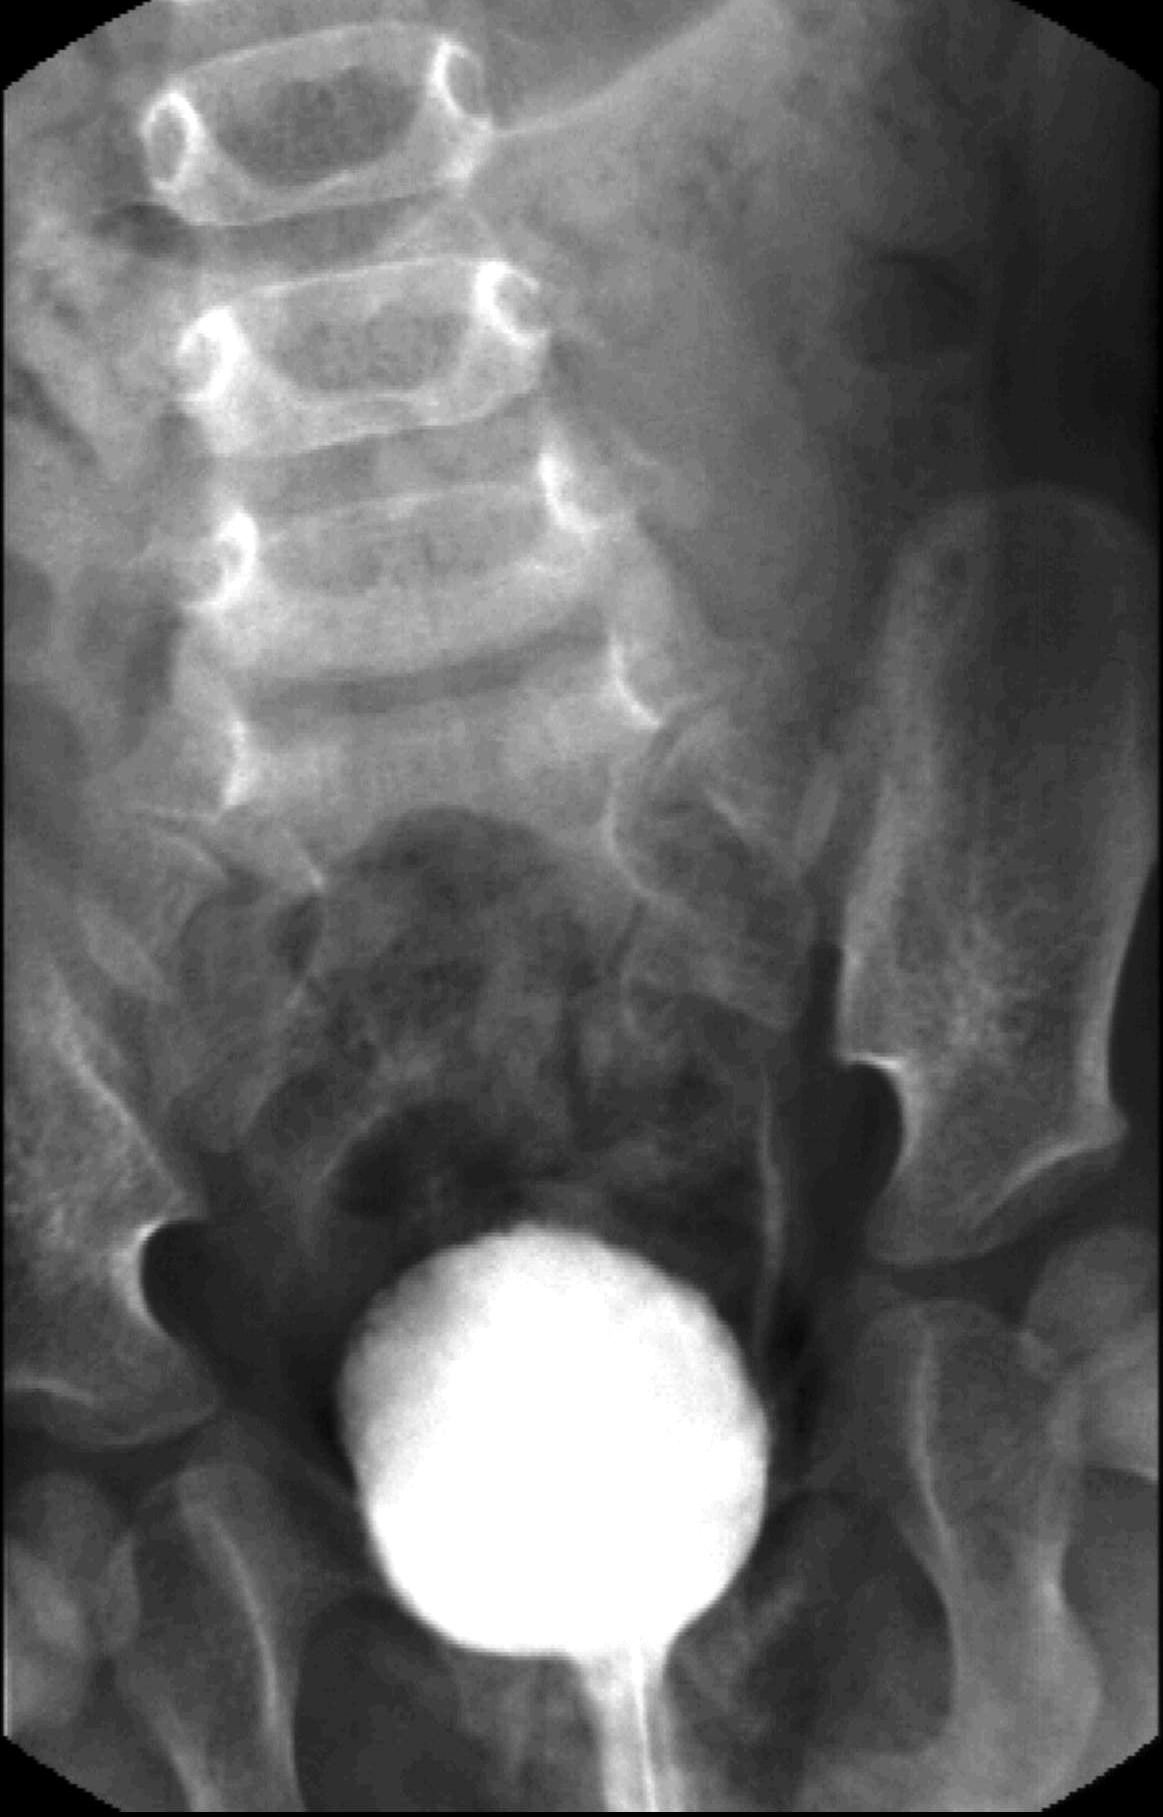

23. Miction cystourethrography. A small diverticula is seen on the right side, the proximal urethra is dilated, beneath is a filling defect. Subvesical obstruction, dorsal urethral valve.

Distal urethral valve (subvesical obstruction). It is the most severe form of obstructive uropathy. In newborn boys the valve dysfunction can lead to bilateral obstruction with hydronephrosis and hydroureter. Urination can only occur intermittently. The bladder wall is thickened, trabecular and reflux is frequent. The proximal urethra is distended as well.